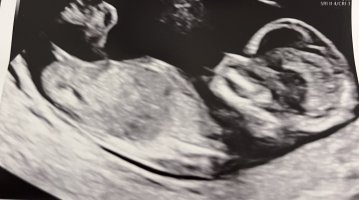

Fikk ikke lagt ved bilde på forrigeJordmor ville ikke si, så vi vet ikke enda..

Synes det ser ut som en liten gutt13+2 og alt bra

Tror ikke det er mulig å se nub her?